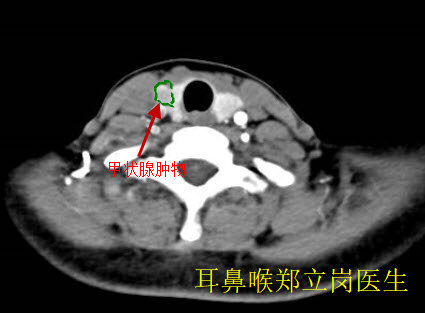

甲狀腺腫物是耳鼻喉的常見疾病,目前發(fā)病率非常高。如果甲狀腺腫物不大,一般無需手術(shù)治療,定期觀察就可以了。如果甲狀腺腫物比較大,就需要及時(shí)的手術(shù)了。傳統(tǒng)的大切口手術(shù)由于外觀不佳,目前處于逐漸的淘汰階段。小切口甲狀腺手術(shù)由于切口小,美觀度好,受到越來越多患者和醫(yī)生的歡迎。最近就有一位結(jié)節(jié)性甲狀腺腫的患者找到耳鼻喉鄭立崗醫(yī)生要求做小切口甲狀腺腫物切除手術(shù)?;颊叨?,女,54歲,廣東佛山禪城人?;颊甙l(fā)現(xiàn)甲狀腺腫物1個(gè)月,由于腫物比較大,這次做的是小切口甲狀腺腫物切除術(shù),麻醉師插管全麻后就開始了手術(shù),在頸前沿皮紋做了一個(gè)大約4cm的小切口,逐漸的分離頸前肌肉后暴露甲狀腺。先做甲狀腺右葉的探查,未見明顯的腫物,再做甲狀腺左葉的探查,可見下中極直徑3cm的腫物,予以切除。傷口止血后予以美容縫合。整個(gè)的手術(shù)用時(shí)約70分鐘,非常的順利,術(shù)后查房患者無明顯的不適,無出血、呼吸困難、聲音嘶啞等病癥。甲狀腺腫物手術(shù)從手術(shù)的時(shí)間、美觀等角度考慮,小切口甲狀腺微創(chuàng)手術(shù)是一個(gè)比較好的選擇。如果您還有什么問題,歡迎留言和耳鼻喉鄭立崗醫(yī)生進(jìn)一步交流。